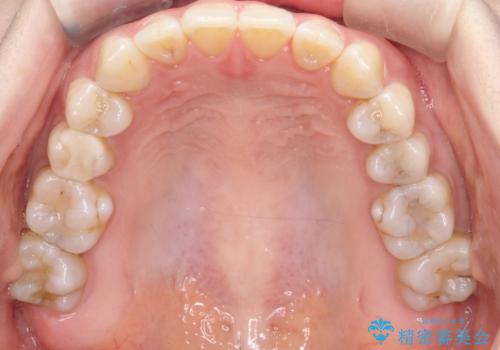

【インビザライン 】前歯の凸凹をなおしたい

- 前歯の凸凹を主訴に来院されました。

インビザライン にて治療を行い、歯並びが綺麗になったと満足していただきました。

前歯のガタガタの量が多かったため、IPR(歯のサイズを小さくするための処置)を行なって治療しました。